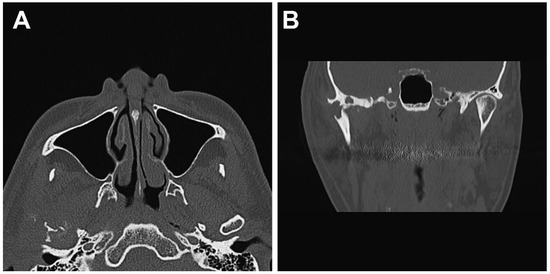

2. Case Presentation

2.1. Clinical Summary

2.2. Pathological Findings